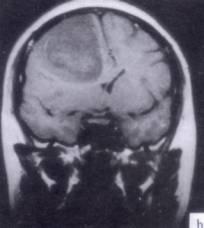

问题 病历摘要:??患者男性,52岁。头痛伴呕吐2月,呕吐呈喷射性。既往身体健康。体检:神清,表情淡漠,反应迟钝,双眼底视神经乳头明显水肿,左鼻唇沟稍浅,左腹壁反射减弱,左上下肢肌力4级,左Babinski征(-)。 为明确诊断,可申请哪些辅助检查?

选项 A.内分泌功能检查 B.脑电图 C.头颅平片 D.头颅MR E.TCD F.SPECT G.CT H.PET

答案 DG